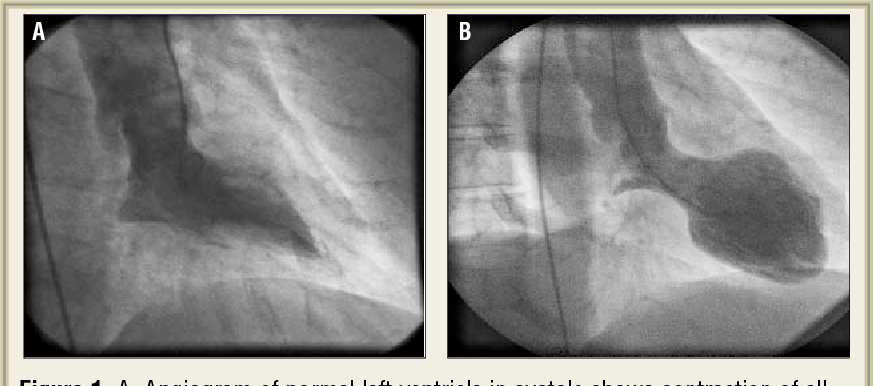

Broken heart is not just metaphorical. There is an actual condition that goes by this name. The precipitants of broken heart syndrome are sudden physical stress, emotional stress, and rapid weakening of heart muscles. Broken heart syndrome is also known as Takotsubo Cardiomyopathy. The signs and symptoms of broken heart syndrome are: - Angina - Pleural effusion - Dyspnea - Arrhythmias - Hypotension Reference: https://my.clevelandclinic.org/health/diseases/17857-broken-heart-syndrome#:~:text=Broken%20heart%20syndrome%20is%20a,weakening%20of%20your%20heart%20muscle. Image via: https://www.semanticscholar.org/paper/The%22broken-heart-syndrome%22%3A-understanding-Takotsubo-Derrick/d827cef92e7265e952dddf11bcf95aa5e779f876